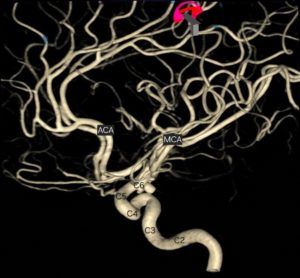

- 緊急磁力共振MRI造影對於在中風黃金小時內進行準確診斷至關重要,尤其是對於缺血性中風。

- MRI 可提供腦部及其血管的詳細影像,從而評估中風類型。

- MRI 亦可顯示缺血性中風時血管阻塞的部位和範圍,或出血性中風時出血的部位和範圍,從而提供選擇合適治療方案的指導。